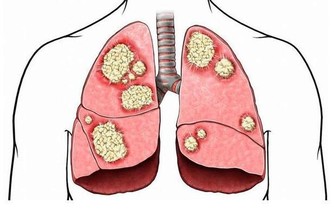

5、口腔白斑

是口腔對外界刺激的最直接反應,假牙不合適、經常抽煙、長期風吹日曬都可能導致這種口腔疾病。

多發於唇、舌、牙齦和舌底,早期並無不適感,如果發生糜爛或潰瘍,會有強烈的疼痛感,但如果繼續惡化,斑塊突然快速增大增厚,這時就要特別小心了,可能是癌前病變的信號。